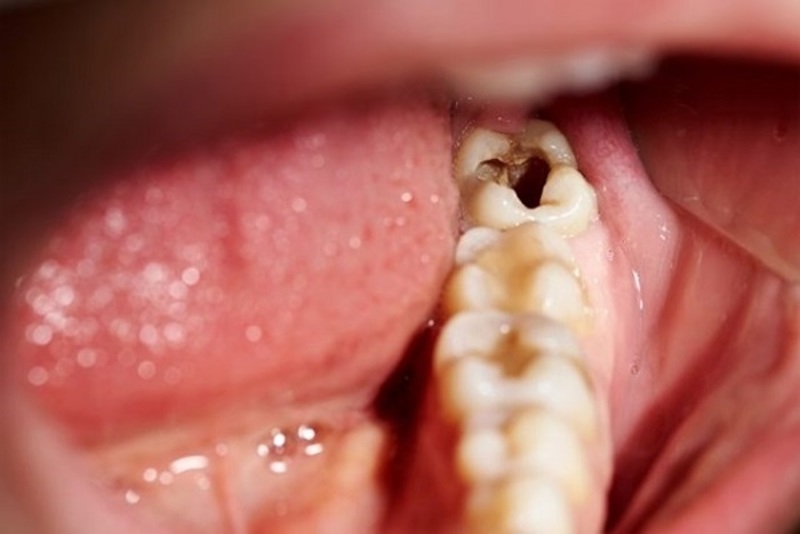

Răng số 8 mọc lệch thường làm hỏng răng bên cạnh là răng số 7. Tình trạng mọc lệch hình thành nên khe hở giữa răng khôn và răng số 7 dễ làm kẹt lại thức ăn, khiến khó vệ sinh, lâu ngày chắc chắn gây ra sâu răng. Khi răng khôn mọc lệch làm ép vào răng bên cạnh làm tiêu biến mất một phần thân và chân răng này.

Quá trình tổn thương có thể diễn ra trong âm thầm kéo dài trong nhiều năm, và cho đến khi bạn phát hiện ra thì tổn thương đã lan rộng gây biến chứng nặng. Khi đi đến phòng khám kiểm tra thì đôi khi răng số 7 đã bị hỏng, hư hại nặng không thể giữ lại được.

Trong khi đó bạn cần phải biết rằng răng số 7 (hay còn gọi là răng hàm lớn thứ hai) là một trong những răng giữ chức năng ăn nhai quan trọng nhất ở trên cung hàm.